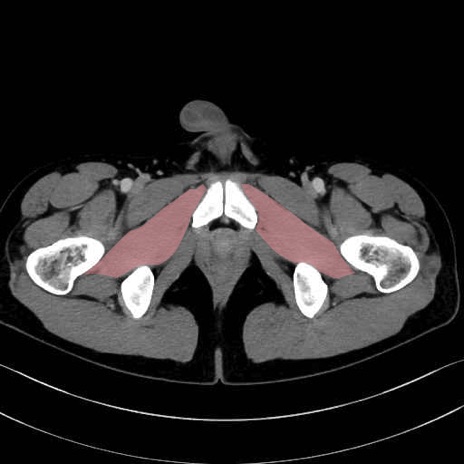

外閉鎖筋(obturator externus) のCT画像の解剖

外閉鎖筋 (Obturator externus)